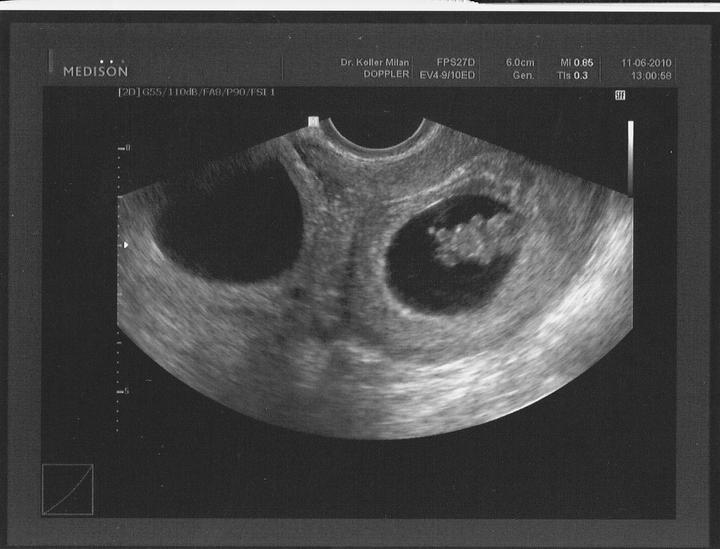

Při druhém pokusu jsme se s doktorkou dohodly, že nastoupím na dlouhý protokol, aby se mi vytvořilo víc kvalitních vajíček. Začala jsem stimulovat od půlky února a koncem dubna šla na odběr folikulů. A taky že to pomohlo, vytvořilo se víc kvalitních vajíček. V Sanatoriu jsem řekla embryologovi, jaký jsem měla posledně problém, a sama mi nabídla, že teda necháme PK na 5 dnů, aby viděli, jak se vyvýjejí a jak to zvládají. 1.5.2010 jsme si jeli do Prahy pro naše embroušky, dokonce vydrželi ještě další dva, které mi dali zamrazit do zálohy.